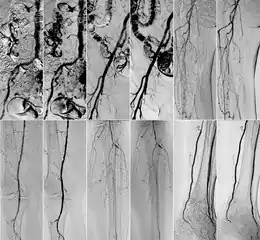

Comparison of kinetic images(KIN) and DSA images in abdominal (top row) and iliac regions (bottom row).

DSA (left) and DVA (KIN, right) image pairs, which were created by administering iodinated contrast agent. From top to bottom: abdominal, iliac, femoral, popliteal and crural regions.

In 2018 Gyánó M. et al. compared the quality of DVA and DSA (digital subtraction angiography) images in a prospective observational crossover study, which involved the analysis of 232 image pairs of 42 patients undergoing lower limb x-ray angiography (performed by using iodinated contrast agent) between February and June 2017. Methods included the measurement of SNR (signal-to-noise ratio) and visual quality comparison.[1]

Although other factors like spatial resolution, sharpness, and object size may contribute to image quality and object perceptibility, noise places a fundamental limitation on the ability to recognize structures on low-contrast images and that was the main reason why the SNR measurement method was chosen. The results showed 2-3 times higher SNR values in the case of DVA images compared to traditionally used DSA images, which has indicated that DVA has the potential to improve the ability to view blood vessels, since a higher SNR value indicates lower noise levels.

Qualitative comparison has been performed by three vascular surgeons and three interventional radiologists, with about 17 years of experience on the average. In an online visual questionnaire, which showed DVA and DSA image pairs of the same anatomical regions, raters were asked to choose the image which they found to be more useful for making the diagnosis. Overall, the raters judged the kinetic images better in 69% of all images. Regarding different anatomical regions, the raters agreed that the DVA was significantly better for talocrural and popliteal regions.

Since the SNR is proportional to radiation dose, the authors have concluded that the higher SNR values indicate that the DVA method has the ability to generate angiographic images which have the same quality as the currently used DSA, but the dose of the administered radiation and/or contrast media could be lowered to achieve the same vessel visibility.